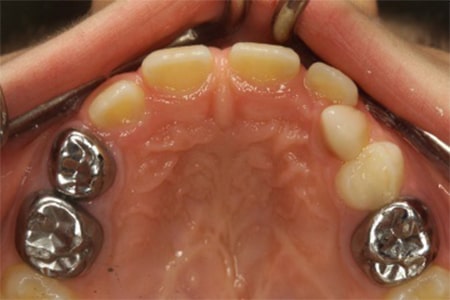

- روکش دندان

یک روکش استیل بر روی ساختار باقی مانده تاج، چسبانده می شود تا کودک بتواند از دندان برای جویدن استفاده کند و هم این که از دندان محافظت شود.